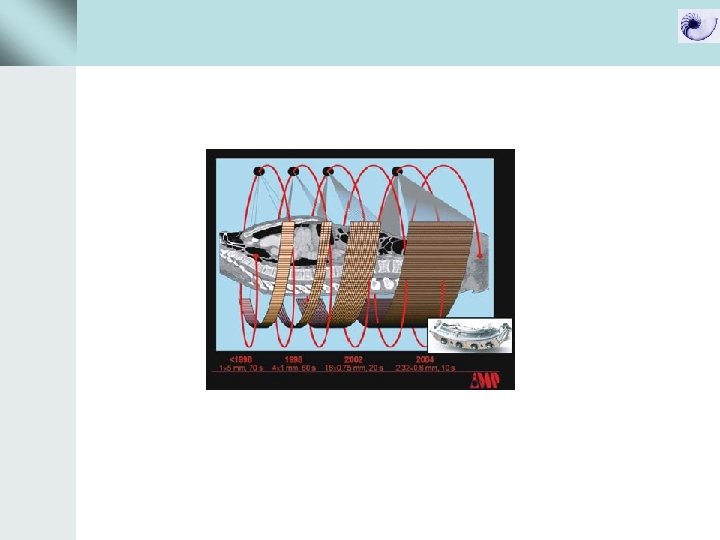

Περιστροφή – spiral path Slip-ring

Data acquisition με συμβατικό CT και spiral CT